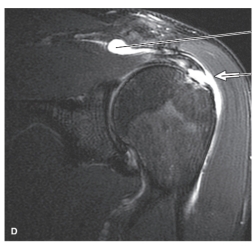

7

-Refer to the figure. Identify the imaging modality and plane.

A) Oblique coronal MRI

B) Coronal MRI

C) Oblique coronal CT

D) Coronal CT

8

-Refer to the figure. Contrast has been added to the ______________joint. This procedure is called _________________.

A) glenohumeral; myelography

B) acromioclavicular; arthrography

C) coracoclavicular; arthrography

D) glenohumeral; arthrography

9

-Refer to the figure. The most common reason this image is made is to identify:

A) Occult or stress fractures

B) Osteochondritis dissecans

C) Labral or ligamentous tears

D) Glenohumeral dislocations